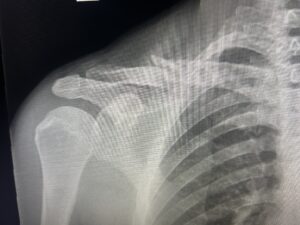

About 4 miles into the ride, I clipped my son’s rear tire and went down hard. I knew before I hit the ground that I was about to break my first bone. I landed forcefully on my shoulder and head. When I stood up, I could feel my collarbone moving in ways God never intended.

I try to make much more specific requests and prayers since that accident. I really messed up my shoulder! My clavicle was broken into 8 pieces, I tore my biceps tendon, had a concussion, and an enormous road rash that tore flesh off my leg.

That said, I was amazed by my recovery. I went to 2 shoulder specialists and they both concurred that my break would heal on its own. So I hammered away at the cold laser/infrared light therapy we have at our office (this speeds up healing and decreases pain and inflammation) and religiously took these bone protocol supplements: